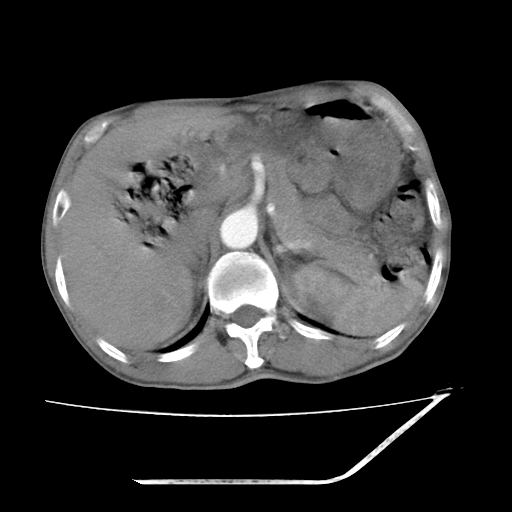

增强

考虑右肾盂癌,肾动脉受侵,右肾功能减退,右肾盂输尿管积水,管壁增厚,考虑种植转移,应该把下面扫完的

支持右侧肾盂癌伴肾静脉瘤栓形成可能性大,右肾结石.肝右叶后段低密度影,不除外转移.

右肾囊实性占位,支持肾癌,窗宽窗位不是很理想

右肾盂旁ca并肾静脉瘤栓形成/肾功能降低。

右肾结石。

支持 右侧肾盂癌伴肾静脉瘤栓形成可能性大,右肾结石;肝右叶后段低密度影,不除外转移。

1.右侧肾盂癌伴肾盂积水。

2.肾脏功能减退,原因有:(1)肾动脉受侵。(2)肾静脉受侵(3)肾积水,等。本例,肾动脉显影较好,但受压明显;肾静脉无明显显示,受压或静脉癌栓,下腔静脉腔内未见明显充盈缺损。